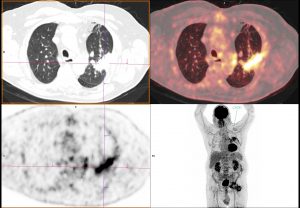

Voici les images MIP de face et de profil de la TEP au 18-FDG

J’ai rajouté les images TDM.

Même si ça paraît étonnant : Réaction granulomateuse sur matériel de drainage pleural en position intraparenchymateuse pulmonaire (laissé en place lors de la chir cardiaque de 2015?)

Bingo !

Effectivement, un drain à été laissé en place lors de la chirurgie cardiaque de 2015.

Son trajet est intra-parenchymateux pulmonaire et se termine au niveau de la paroi thoracique gauche.

Au niveau de son passage intercostal, il a entrainé un pont osseux intercostal entre les côtes sus et sous jacentes.

Pour l’instant, pas de contingent néoplasique mis en évidence.